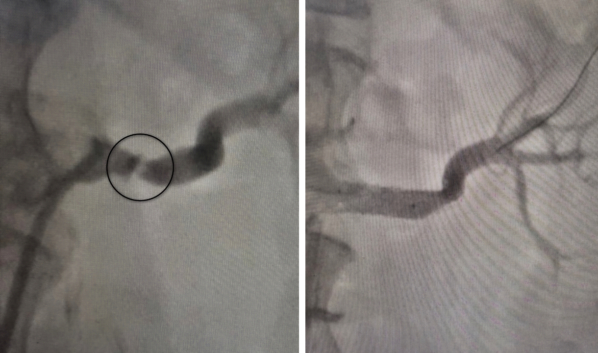

До операции и после.

Для дальнейшего лечения пациентку перевели в областную клиническую больницу №1. Там ей выполнили ангиографию почечных артерий, которая подтвердила сужение сосуда до 80 процентов. Под руководством врача отделения рентгенхирургических методов диагностики и лечения Ивана Тимошина женщине провели баллонную ангиопластику и стентирование поражённой артерии.